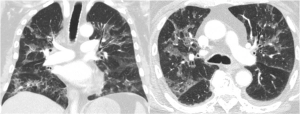

Pneumocystis jirovecii Pneumonia in Patients With Metastatic Prostate Cancer on Corticosteroids for Malignant Spinal Cord Compression: Two Case Reports and a Guideline Review

Two case reports and a review of PCP in patients with solid tumors.